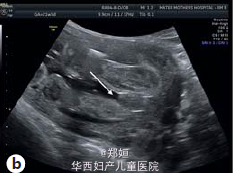

22岁初产妇,孕21周,因胎儿膀胱未见、羊水过少、胎儿腹部囊性结构就诊

B超提示羊水过少和未见胎儿膀胱,肾窝内未见肾脏,但是在腹腔和盆腔可见三个囊性结构,外生殖器性别不明 胎儿MRI提示有泌尿生殖器畸形

临床诊断为胎儿泌尿生殖器畸形 患者要求生产,在孕35周,顺产生下一3140g男婴